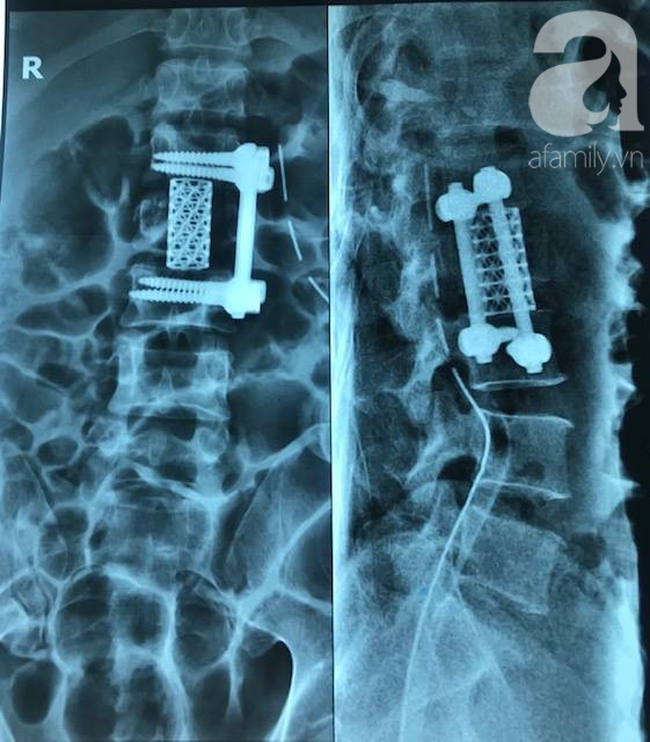

Phần lưng: gãy nhiều mảnh đốt sống L2 và có mảnh lùi chèn vào tủy sống gây yếu một phần hai chân và gây bí tiểu và gãy các mấu nang từ đốt sống L3 – L5.

Bác sĩ hàn liên đốt sống cho bệnh nhân.

Bằng sự quyết tâm, 3 ê kíp mổ khác nhau đã hợp sức liên tục trong gần 5 giờ. Bệnh nhân được phẫu thuật giải ép, hàn liên đốt sống, phẫu thuật kết hợp xương đùi, xương gót, bó bột cẳng chân và nắn chỉnh các xương gãy.